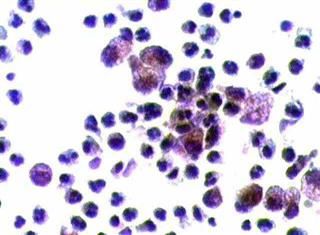

Aσθενής 45 ετών, με γνωστή παρουσία πολλαπλών κύστεων και στους δύο μαστούς εδώ και πολλά χρόνια.. Επώδυνη κύστη διαμέτρου 4 εκ. στον αριστερό μαστό. Κάτω από υπερηχογραφικό έλεγχο παρακέντηση και αφαίρεση περίπου 20 κ. εκ. κιτρινωπού υγρού.